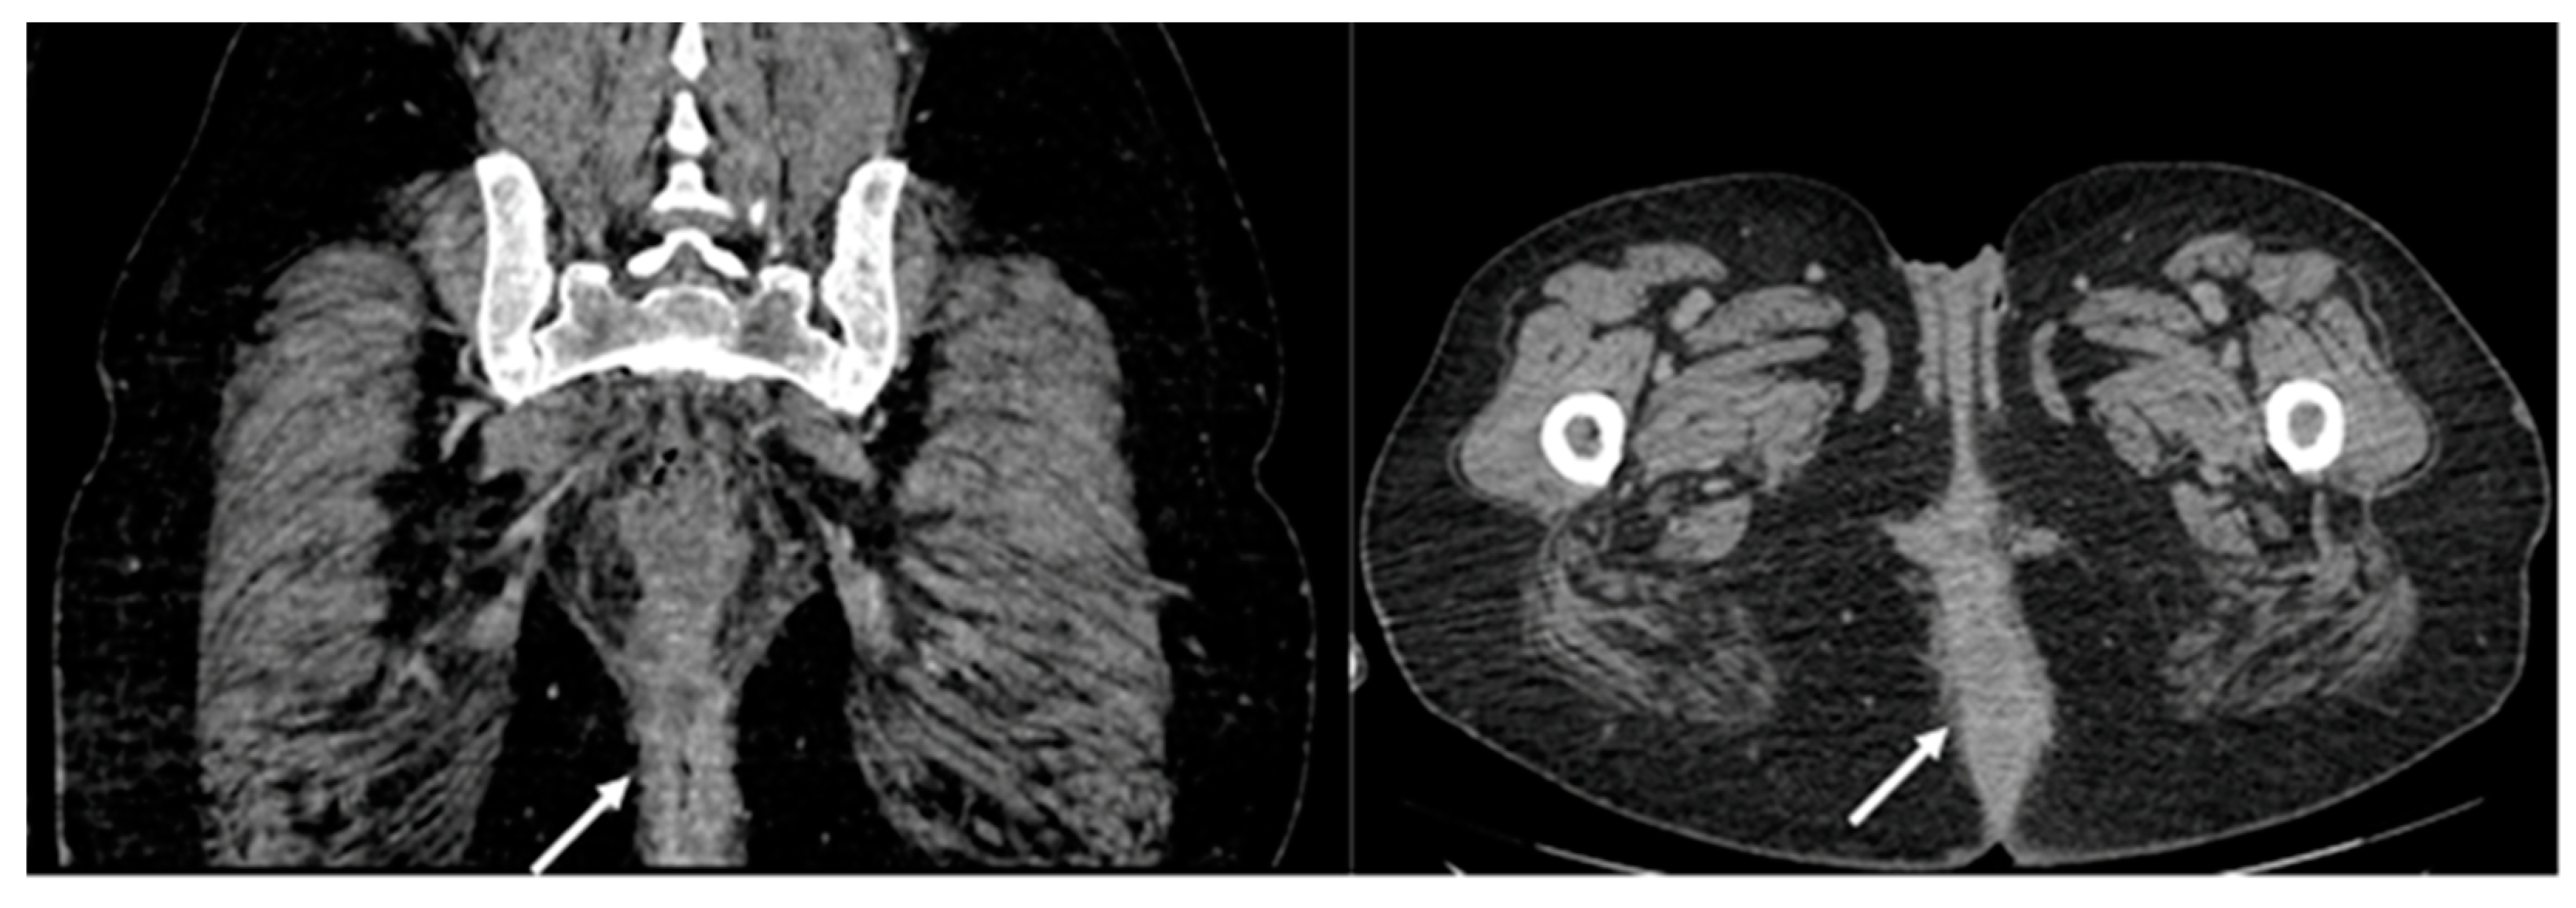

2.1. Case Report